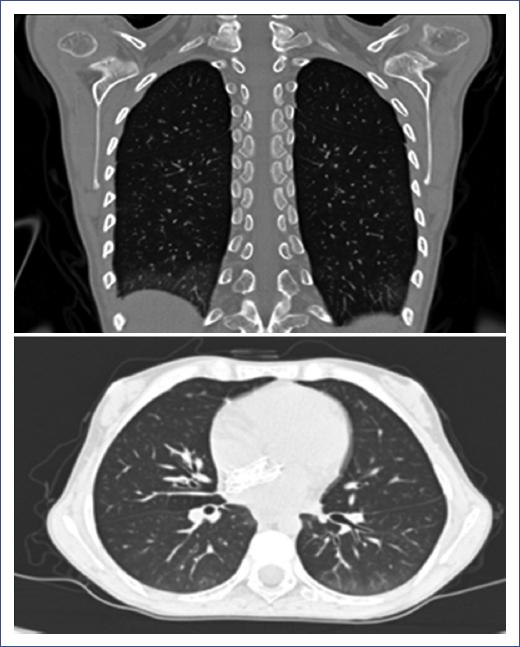

HRCT revealed ground-glass images in almost half of the patients. Only two patients were asymptomatic with no imaging abnormalities. Figure 1 shows the chest HRCT of a patient with JSSc and pulmonary involvement with interstitial thickening, typical of ILD. Four patients (26.7%) with the diffuse variety were positive to anti-topoisomerase I antibodies.

Figure 1 High-resolution computed tomography (HRCT) of a patient with juvenile systemic sclerosis (JSSc) and pulmonary involvement showing interstitial thickening typical of interstitial lung disease (ILD).